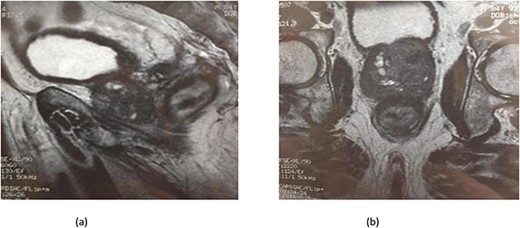

Serum carcinoembryonic antigen was 4.3 μg/L (normal value <5.1 μg/L). Biological tests showed normal platelet count and prothrombin time was 70%. Hemoglobin level was 12.2 g/dL. His biochemical tests showed hypoalbuminemia (31 g/dl). The patient was scheduled for a colonoscopy. However, a large bowel obstruction occurred during the bowel preparation. Thus, computed tomography (CT) scan of the abdomen and the pelvis was performed revealing circumferential wall thickening narrowing the rectal lumen and invading the prostate and the mesorectum with upstream bowel dilatation without extrinsic mass, lymphadenopathy, or metastasis. The patient underwent colostomy without incident. Colonoscopy was performed after colostomy, showing large, circumferential, infiltrative, friable, and stenosing submucosal mass with erythematous overlying rectal epithelium, taking on the appearance of grape clusters (shown in Fig. 1). Mucosal biopsies showed invasive poorly differentiated carcinoma referring at first a neuroendocrine tumor. Second mucosal biopsies were performed showing inflammatory modifications of the rectal mucosa without any malignancy. Third mucosal biopsies concluded to poorly differentiated carcinoma. Magnetic resonance imaging (MRI) of the pelvis showed circumferential wall thickening narrowing the rectal lumen and invading posterior peripheral area of the prostate, the bladder, the left seminal vesicle, and the mesorectum (shown in Fig. 2). The radiologist suggest a rectal cancer (RC) invading the urogenital tract or a PC invading the rectum subject to non-injected MRI. In fact, the MRI was interrupted before gadolinium injection because the patient was claustrophobic. Serum prostate specific antigen (PSA) was then ordered and it was raised at 25.59 μg/L (normal value<4 μg/L). Therefore, macro-biopsies of the rectal mucosa using snare loop were performed showing a poorly differentiated infiltrative carcinoma and immunohistochemical (IHC) stains were strongly positive for PSA and pancytokeratin and negative for anti-CD56 (shown in Fig. 3). Then, a clear diagnosis of PC invading the rectum was established. Bone scintigraphy was performed and was normal. The patient was referred to urology department. He underwent surgical castration. Then, androgen depletion therapy (ADT) was started. A total of 3 months later, there was a good response with his PSA level dropping to 0.5 μg/L. About 3 years after, patient is still alive, but PSA level has increased to 52 μg/L. The CT scan of the thorax, the abdomen, and the pelvis showed a prostatic hypertrophy with loss of the security edging with the rectum without any metastatic involvement.

(a) MRI features: circumferential wall thickening narrowing the rectal lumen and invading the prostate and the mesorectum without extrinsic mass on sagittal section of the pelvis. (b) MRI features: a cross section of the pelvis showing circumferential wall thickening narrowing the rectal lumen and invading the prostate and the mesorectum.

In our case, the patient experienced digestive symptoms without any lower urinary tract symptoms. Colonoscopy findings were uncommon showing a circumferential, infiltrative, friable, and stenosing submucosal mass, taking on the appearance of grape clusters. In historically reported cases, the diagnosis of PC was confirmed by histology obtained by endoscopic ultrasound with transrectal needle biopsy of the prostate or surgical biopsies [6]. In our case, PC invading the rectum was suspected after CT scan and MRI. Serum PSA was not requested in the beginning but seeing the radiological findings; it was ordered and was high suggesting a PC. Histology was not contributive initially at three times, what prompted us to perform macro-biopsies of rectal mucosa showing a poorly differentiated infiltrative carcinoma. The IHC stains were strongly positive for PSA.